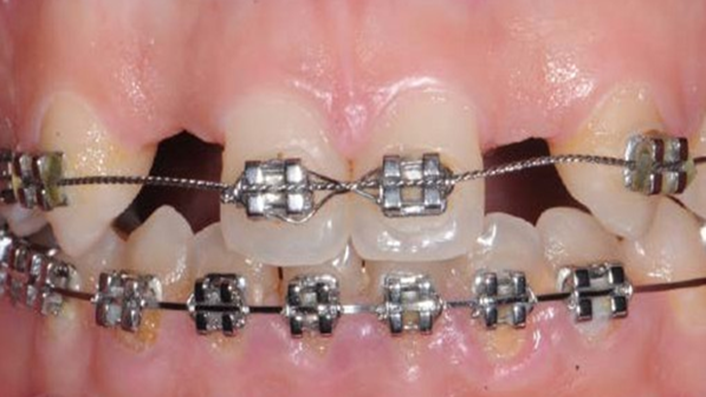

Clinical case: Patient-centered approach: treatment strategy for Root Membrane Technique & delayed implant placement

- Courtesy of Dr. Yoshiharu Hayashi, Japan -

Socket Shield Technique, anterior esthetics, maxillary anterior, esthetic, esthetics, delayed implant placement, socket preservation, AnyRidge, Root Membrane Kit, Root Membrane Technique, Partial Extraction Therapy, PET, esthetic zone, fuse abutment, Dr. Yoshiharu Hayashi,#11,#21,#22

Products:

AnyRidge implant system, fuse abutment Root membrane kit, PET Kit